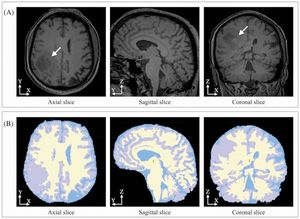

Publication: PLoS One. 2015 Oct 7;10(10):e0139323. PMID: 26445367 | PDF Authors: Cadotte A, Cadotte DW, Livne M, Cohen-Adad J, Fleet D, Mikulis D, Fehlings MG. Institution: Department of Surgery, Division of Neurosurgery, University of Toronto, Toronto, Ontario, Canada. Background/Purpose: Spinal cord segmentation is a developing area of research intended to aid the processing and interpretation of advanced magnetic resonance imaging (MRI). For example, high resolution three-dimensional volumes can be segmented to provide a measurement of spinal cord atrophy. Spinal cord segmentation is difficult due to the variety of MRI contrasts and the variation in human anatomy. In this study we propose a new method of spinal cord segmentation based on one-dimensional template matching and provide several metrics that can be used to compare with other segmentation methods. A set of ground-truth data from 10 subjects was manually-segmented by two different raters. These ground truth data formed the basis of the segmentation algorithm. A user was required to manually initialize the spinal cord center-line on new images, taking less than one minute. Template matching was used to segment the new cord and a refined center line was calculated based on multiple centroids within the segmentation. Arc distances down the spinal cord and cross-sectional areas were calculated. Inter-rater validation was performed by comparing two manual raters (n = 10). Semi-automatic validation was performed by comparing the two manual raters to the semi-automatic method (n = 10). Comparing the semi-automatic method to one of the raters yielded a Dice coefficient of 0.91 ± 0.02 for ten subjects, a mean distance between spinal cord center lines of 0.32 ± 0.08 mm, and a Hausdorff distance of 1.82 ± 0.33 mm. The absolute variation in cross-sectional area was comparable for the semi-automatic method versus manual segmentation when compared to inter-rater manual segmentation. The results demonstrate that this novel segmentation method performs as well as a manual rater for most segmentation metrics. It offers a new approach to study spinal cord disease and to quantitatively track changes within the spinal cord in an individual case and across cohorts of subjects. Funding: |

Examples of difficult segmentations due to reduced CSF, artifacts, and spinal rootlets. In the first four examples, the segmentation performed well. In the next two examples (third and fourth rows), applying a smoothing filter improved the segmentation result due to reduced CSF volume and image artifacts. The semi-automated segmentation method requires initial user input to approximate the center of the non-segmented spinal cord, between the start and end points of the desired segmentation region, using 3D Slicer. |